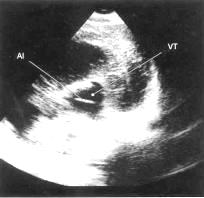

Ультразвукове дослідження головного

мозку (нейросонографія) - це звичайне, недороге обстеження, що допомагає

оцінити ступінь розширення шлуночків мозку. Звукові хвилі проходять через

незаросле тім'ячко, даючи чітку картину шлуночків, що значно полегшує

постановку діагнозу. У старших дітей УЗД не використовується, кістки черепа

перешкоджають проходженню ультразвуку. Виключення складають випадки, коли існує

дефект черепа - отвір, через який можуть проходити звукові хвилі. Метод УЗД

використовується також для внутрішньоутробної діагностики гідроцефалії. Ц,ь,ю)